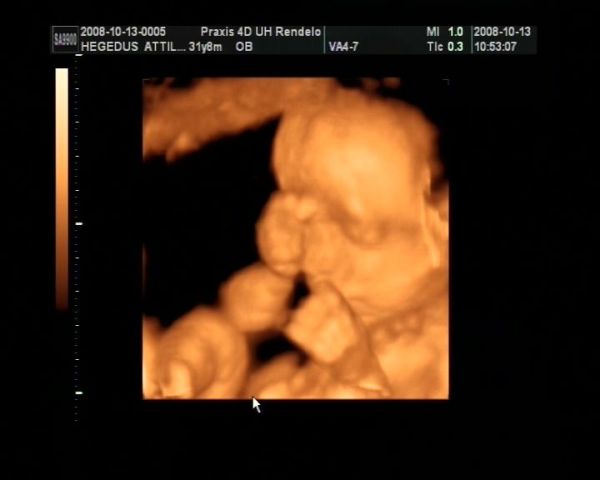

Ez tegnapi